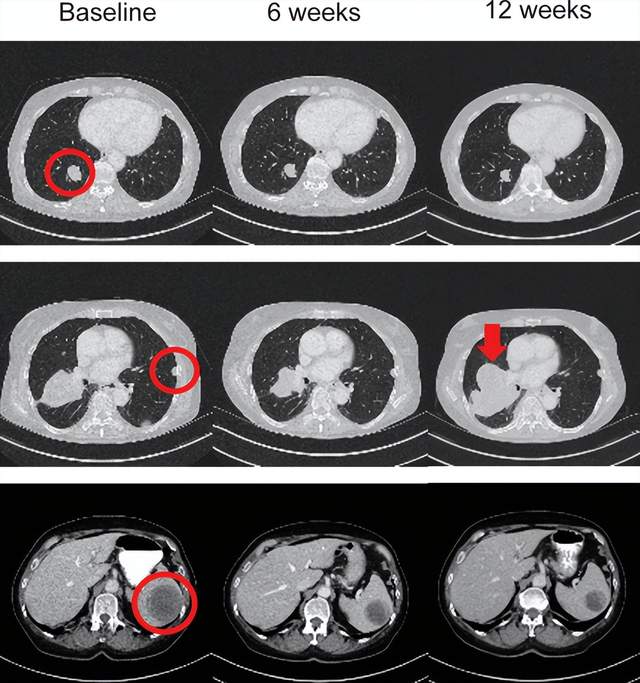

这项1期试验(IMA202-101)共16名患者接受IMA202治疗,7名患者患有黑色素瘤,2名肛门鳞状细胞癌(SCC),2名肝细胞癌,2名非小细胞肺癌(NSCLC),以及骨肉瘤、横纹肌肉瘤和口咽鳞状细胞癌患者各1例。结果显示:11名(68.8%)患者的最佳总体反应是疾病稳定(SD),5名患者的靶病灶总和出现初始肿瘤缩小。其中患者03在第42天评估为病情稳定(SD),在3个月时其靶病灶直径总和进一步缩小了35.4%。

因此,IMA202在MAGEA1阳性复发性和难治性实体瘤中具有一定的临床效果。